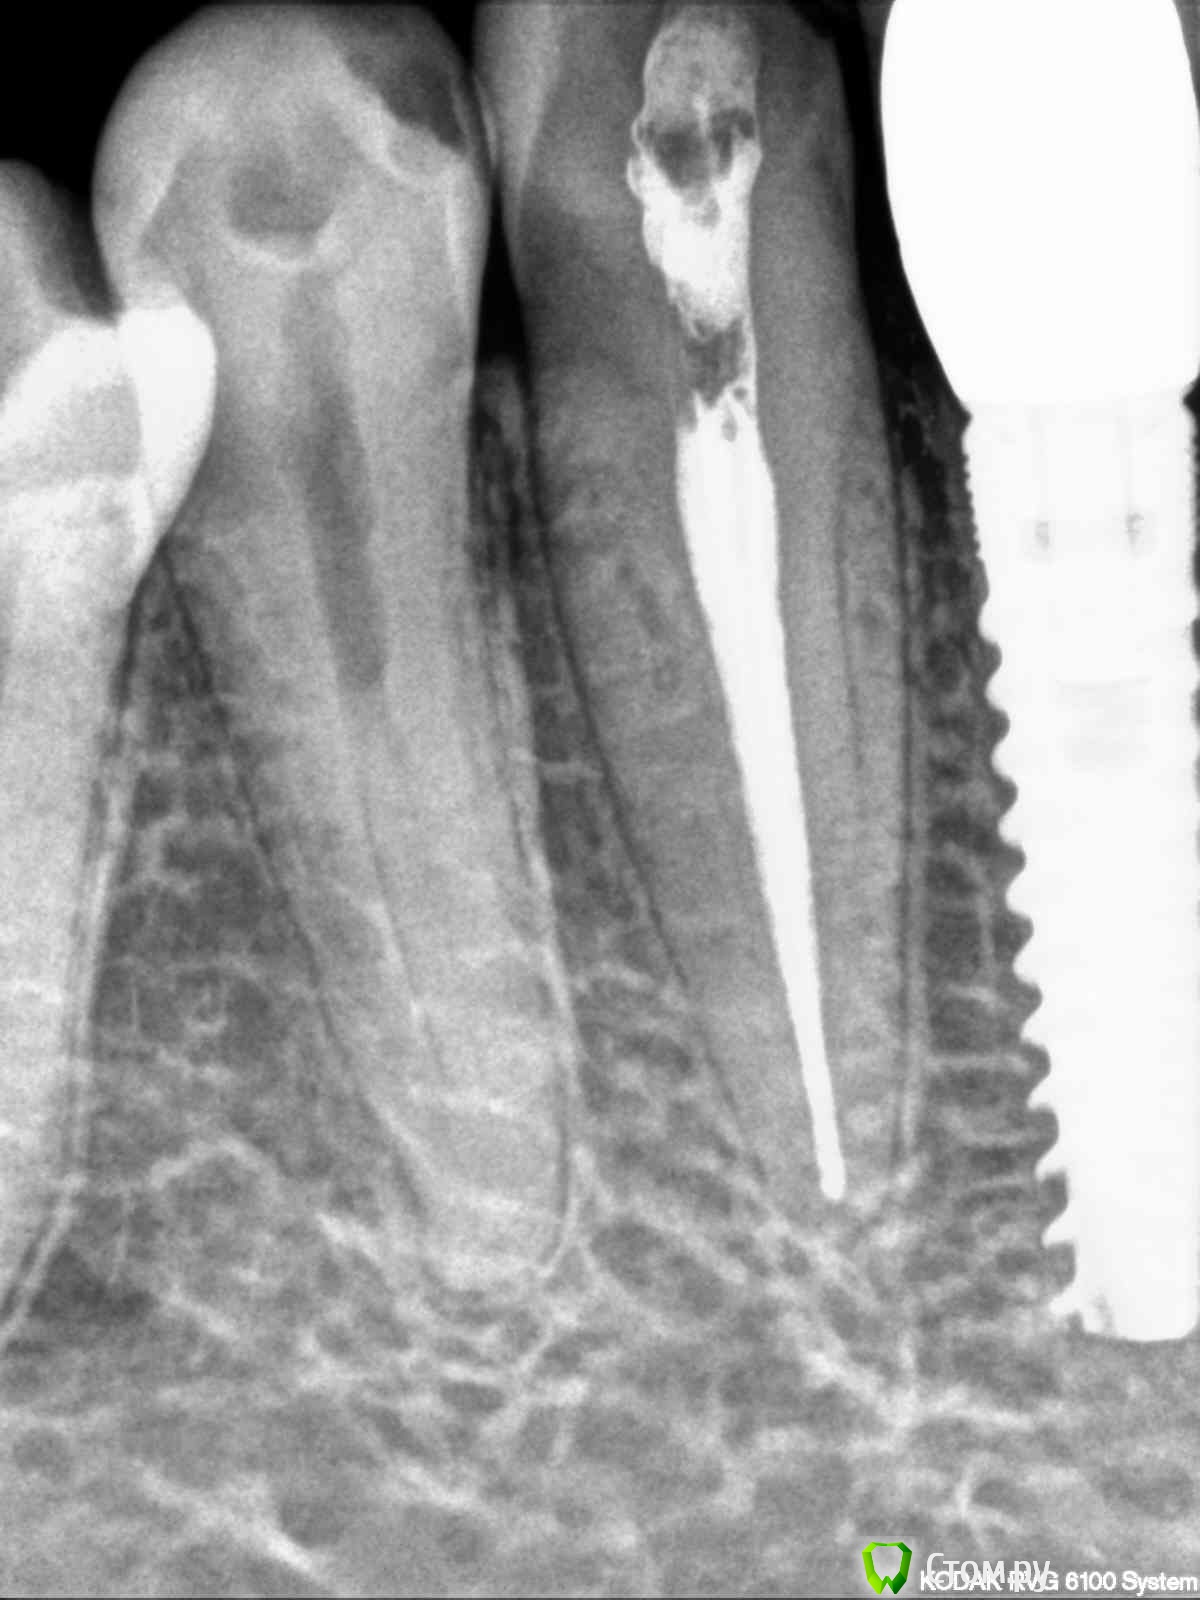

englishlady Опубликовано 16 декабря, 2013 Поделиться Опубликовано 16 декабря, 2013 Уважаемые врачи, здравствуйте. Позвольте Вас еще раз побеспокоить. В зубе 43 полгода назад лечились каналы. Все это время на зубе временная пломба из цемента. На нем даже возможно образовался кариес. Иногда зуб незначительно ноет. Пред дальнейшим лечением (пломба или коронка) есть необходимость в том, чтобы перелечить каналы? Или лучше не трогать. Снимок прилагаю. Заранее спасибо Ссылка на комментарий

IvanK Опубликовано 16 декабря, 2013 Поделиться Опубликовано 16 декабря, 2013 Здравствуйте,выглядит все хорошо,но если ноет - нужно. Вам бы на очный прием, может и не он ноет.. Ссылка на комментарий